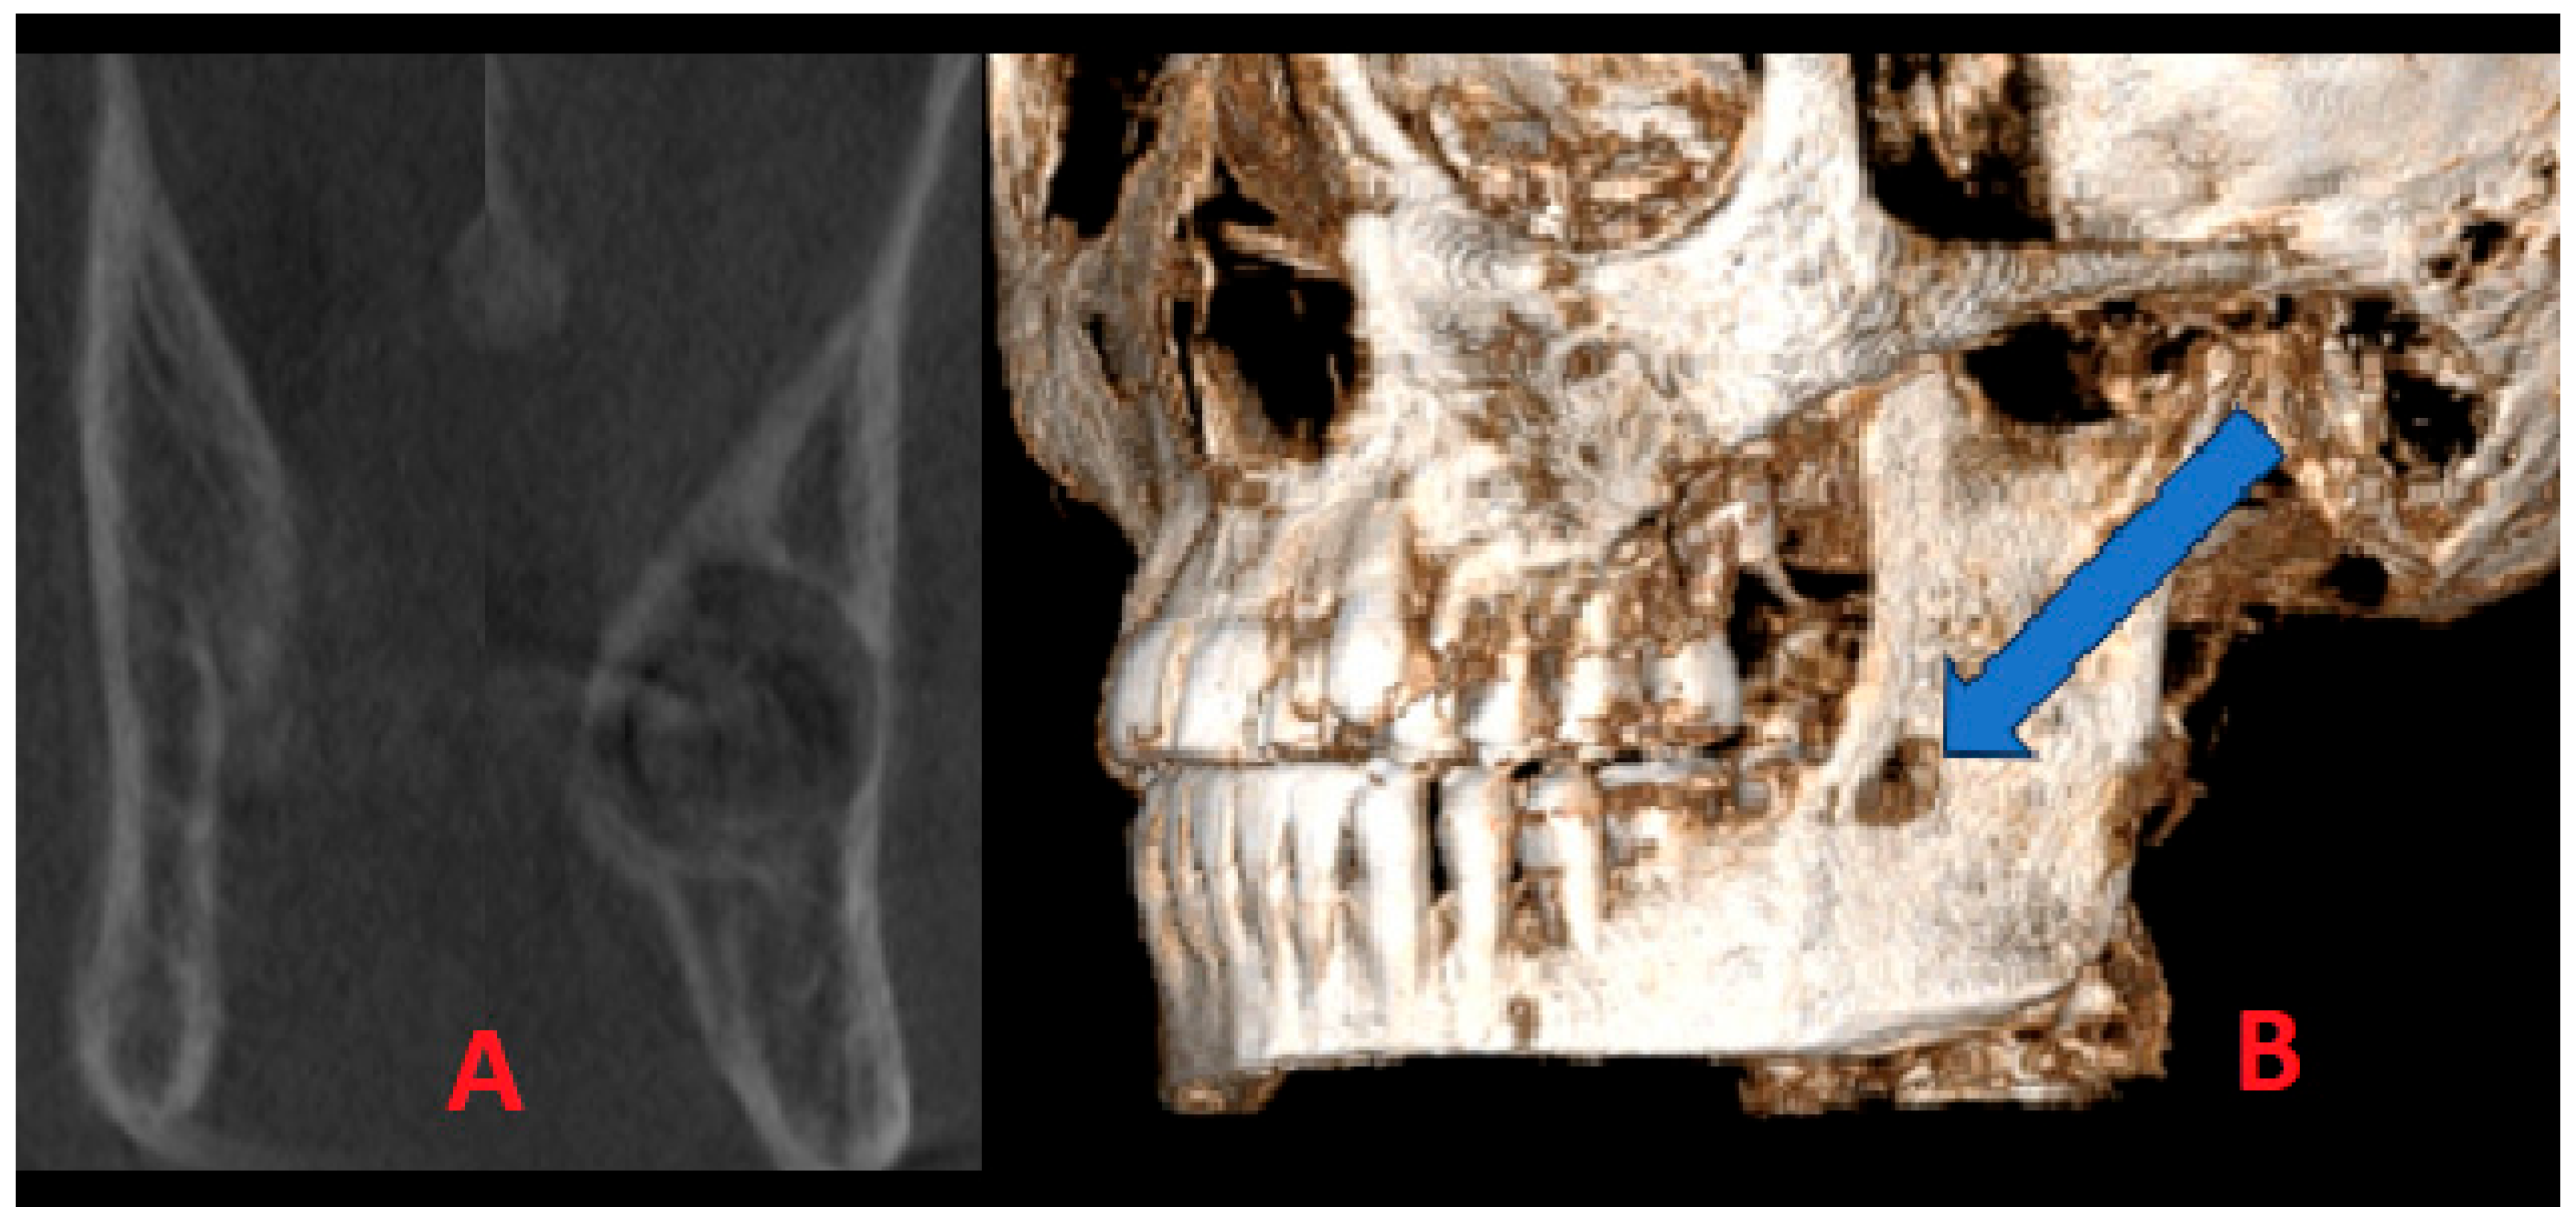

Additional CBCT was carried out to estimate the lesion’s boundaries and shape, the status of the cortical bone, and the proximity of the adjacent second molar, and the condition of the surrounding bones was visualized. A detailed CBCT evaluation of this cystic lesion revealed some worrisome radiological factors; however, no characteristic signs of OM were noted. This finding might be related to early OM detection in the early stages of growth and formation, and it is perhaps related to the remnants of the third molar germ or a bundle of not-yet-visible wisdom molar teeth. On the other hand, OM has a less unilocular appearance typically, which is more common for typical cystic lesions in this area. Coronal scans of both mandibular rami (A) revealed notable cortical enlargement and resorption to the lingual and buccal aspect on both sides of the cortical bone, with lesions penetrating towards the left mandible ramus. In this 3D reconstruction projection (B) of the lesion, clearly visible buccal cortical bone erosion and extra bone spread of the lesion were identified (Figure 4). Since the perforation was present, no typical “sunburst” appearance, characteristic of cortex perforation, and the presence of radiopaque lines extended from the periosteum was found. Another worrisome symptom in CBCT revealed significant bone swelling and asymmetry without the presence of the third molar. The lesion itself was very early in its initial stages of development; therefore, to assess its type and structure, a decision for early surgery was performed.

Figure 4. The CBCT visualization of the lesion: (A) bone asymmetry; (B) extracortical spread marked with blue arrow.